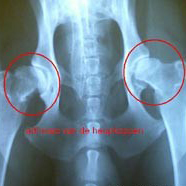

Artrose bij de kat komt vooral voor in gewrichten zoals de elleboog, schouder, heup, knie en wervels.